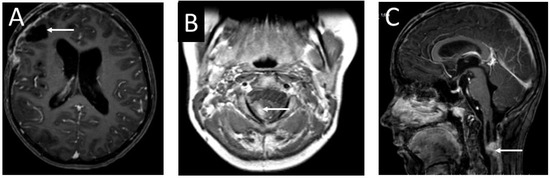

2. Case Presentation